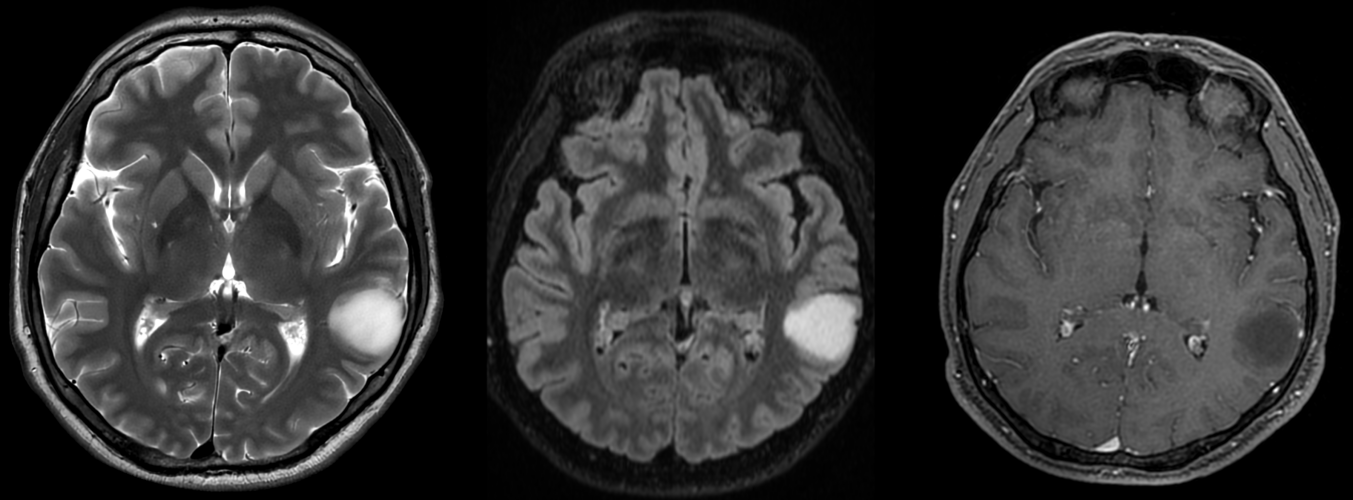

– CT cerebral – util doar ca evaluare inițială; are sensibilitate scăzută și poate trece frecvent cu vederea o tumora de dimensiuni reduse.

Gliom de grad mic de hipocamp stâng – comparație CT – RMN

RMN cerebral cu contrast – metoda standard pentru caracterizarea glioamelor. Glioamele de grad mic apar ca leziuni hipointense pe T1, hiperintense pe T2, fără captare de contrast. În mod uzual se consideră că dacă un gliom de grad mic are o zonă cu priză de contrast pe RMN el este de grad III – anaplazic (grad înalt).